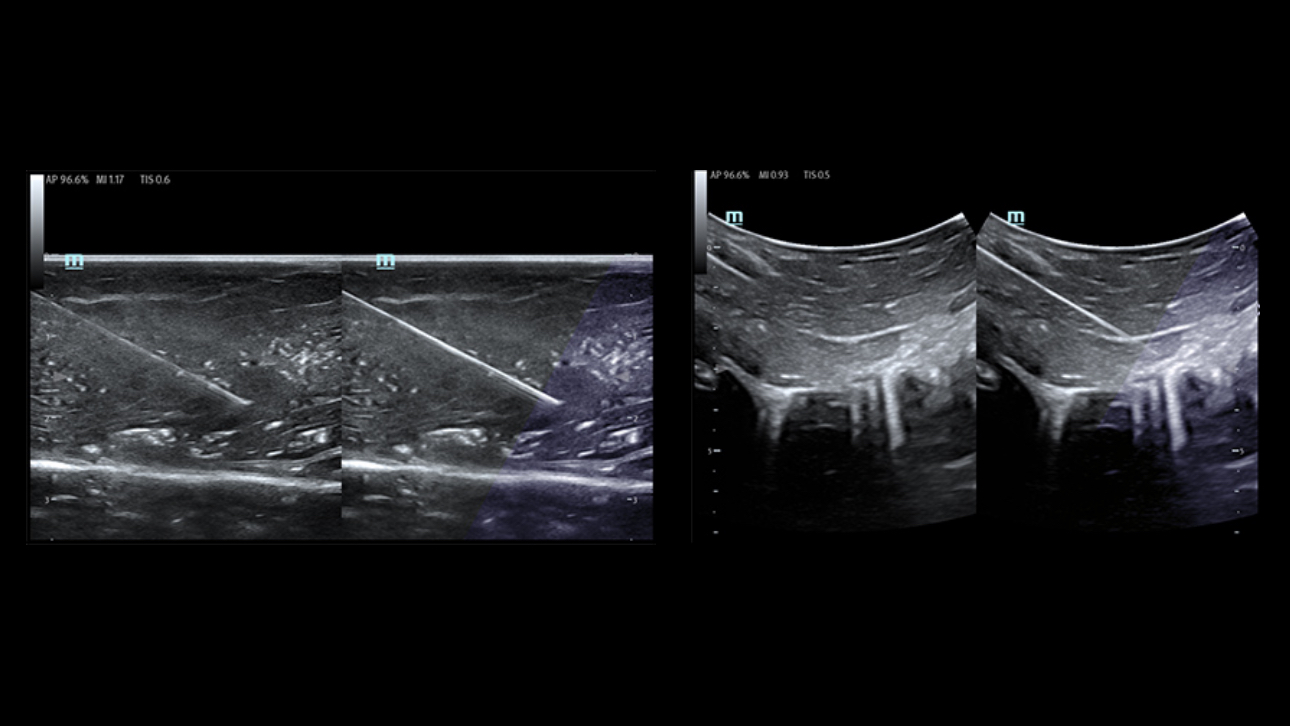

Single Operator Puncture Solution